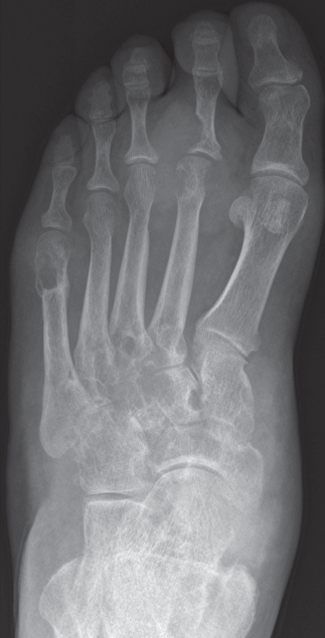

Recurrent acute gout attacks may lead to changes in joint structure visible on plain radiographs. In the x-ray film of the foot below, note the large radiopaque tophus over the second metatarsophalangeal joint and the periarticular punched-out erosions along the long axis of the bone, with overhanging edges and sclerotic rims. Joint space is generally very well preserved until late in the course of disease.